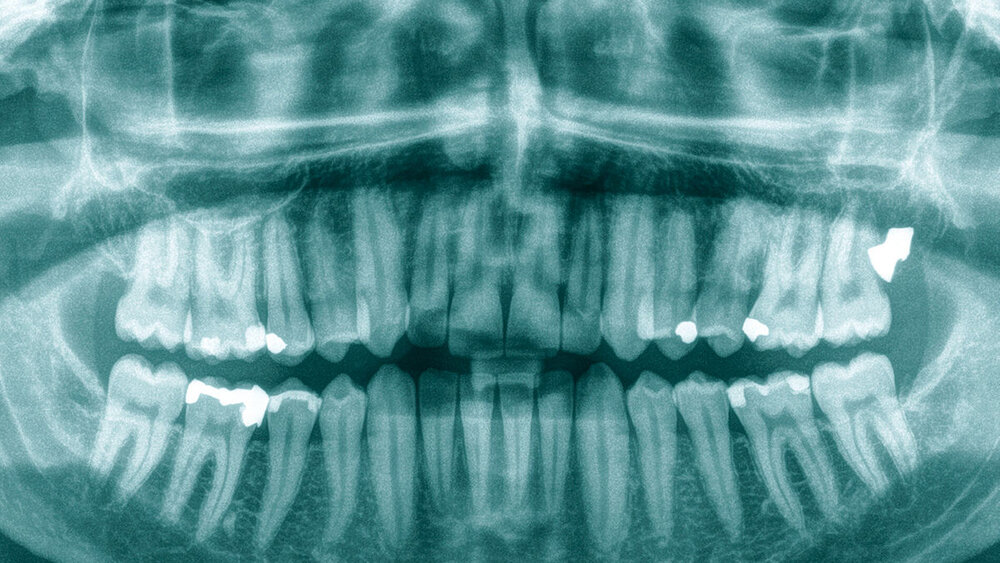

Bei der Erstvorstellung präsentierte sich der allseits gesunde Patient mit Schmerzen im Bereich des linken Kiefergelenks und der angrenzenden Kaumuskulatur. Die Mundöffnung war schmerzhaft auf 19 mm eingeschränkt. Andere CMD-typische Befunde zeigten sich nicht. Die intra- und extraorale Untersuchung war ohne pathologischen Befund. In der Vorgeschichte war ausschließlich die Osteotomie der vier Weisheitszähne alio loco vor einigen Jahren zu finden. Auf Nachfrage wurde ein zeitlicher Zusammenhang mit den Beschwerden geschildert. Zur weiteren Abklärung wurde ein Orthopantomogramm (OPT, Abbildung 1) angefertigt.

Nach Anfertigung des Röntgenbildes erfolgte eine erneute Untersuchung der regiones 27 und 028 und der angrenzenden Weichteile. Weder inspektorisch noch palpatorisch ließ sich der im OPT sichtbare Fremdkörper nachvollziehen, in der Sonografie ließ er sich nicht sicher darstellen. Aufgrund der zu erwartenden Metallartefakte wurde eine Digitale Volumentomografie (DVT) zur Lokalisation des Fremdkörpers durchgeführt, die eine circa 5 mm x 5 mm x 7 mm, stark radioopake Struktur am ehesten im Bereich des Musculus masseter zeigte.

Die differenzialdiagnostischen Überlegungen im Kollegium reichten von einem Artefakt über ein Inlay bis zur Spitze eines Wurzelhebels nach Barry, einem eingesprengtem Schrapnell oder einem Projektil. In der wiederholt durchgeführten Anamnese fanden sich keine Angaben hinsichtlich der Anfertigung eines Inlays oder auf Schuss- oder Kriegsverletzungen. Extraoral fand sich im zu untersuchenden Bereich nur eine winzige Narbe, die in der Gesamtbetrachtung am ehesten auf die Folgen einer juvenilen Akne zurückzuführen war.